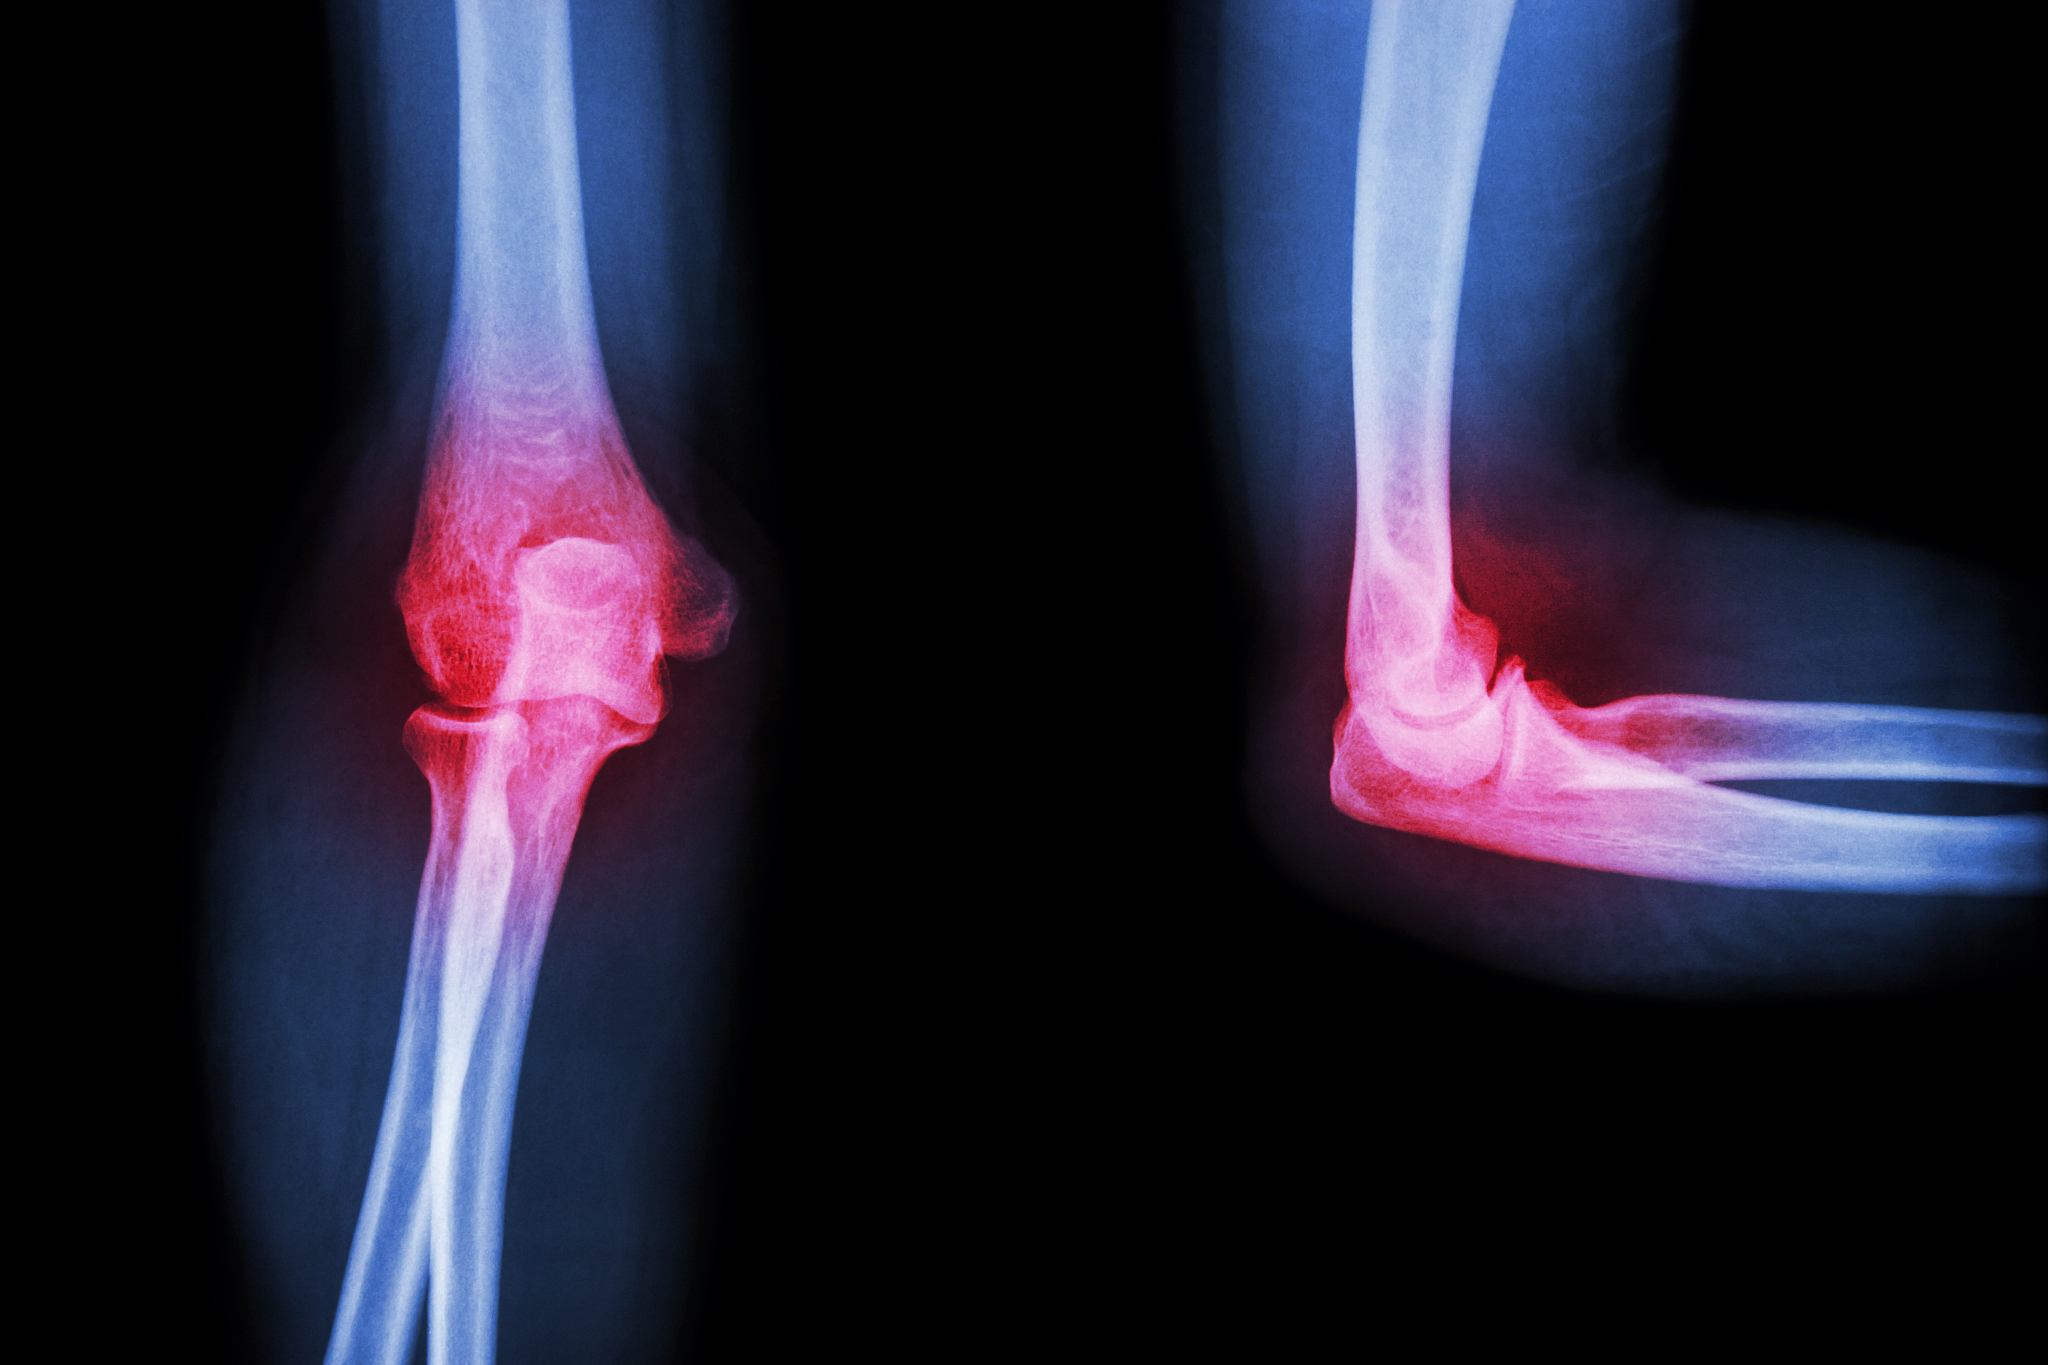

肱的相关疾病

肱部的疾病包括肱骨骨折、肱骨头坏死以及肱骨滑囊炎等。肱骨骨折一般由外力打击导致,常见于运动员和老年人。肱骨头坏死则是由于肱骨头的供血不足而引起的骨质坏死。肱骨滑囊炎则是由于肩袖肌群的过度使用而引起的肩部疼痛。